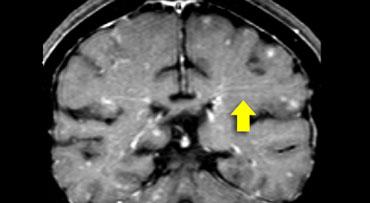

Sarcoid

Sarcoid đã vượt qua giang mai thần kinh để trở thành “kẻ giả mạo vĩ đại” trong chẩn đoán hình ảnh thần kinh.

Phân bố tổn thương trong trường hợp này khá tương đồng với MS.

Ngoài các tổn thương ở chất trắng sâu, còn có một số tổn thương cạnh não thất và thậm chí các tổn thương dạng ngón tay Dawson.

Tuy nhiên, chẩn đoán cuối cùng là sarcoid.

Một đặc điểm điển hình khác trong trường hợp này là hình ảnh ngấm thuốc dạng tuyến (mũi tên vàng).

Điều này là do viêm dọc theo khoang Virchow-Robin.

Đây cũng là một dạng ngấm thuốc màng não mềm.

Điều này giải thích tại sao sarcoid có phân bố tương tự MS: các khoang Virchow-Robin đi theo các tĩnh mạch xuyên nhỏ, vốn là những cấu trúc bị tổn thương trong MS.